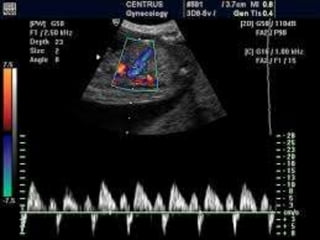

Umbilical vein

• The umbilical vein should be examined either

within the fetal abdomen or in the umbilical

cord

• The flow is constant from 12 weeks onwards

in 90% of the fetuses

• Monophasic pulsations are relevant if central

veins are abnormal

• Clinical application of umbilical venous

Doppler: fetal growth restriction, twin-to-twin

transfusion syndrome and hydrops fetalis

• Pulsations are observed in 10% of fetuses and

these can be:

• Monophasic

• Biphasic

• Triphasic

• Multiphasic pulsations indicate abnormally

high venous pressure